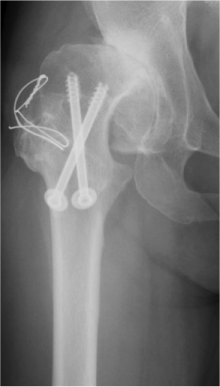

高位脱臼に対する人工関節

生まれつき股関節が脱臼した状態で気づかずに放置されていた場合、正常な股関節より高い位置に関節が形成されていることがあります(高位脱臼)。脱臼した側の足の長さは5~6cm短くなっていることが多く、関節が変形し、痛みが出やすい状態になります。

このような場合、大腿骨を数cm切り取り(短縮骨切り術)、正常な関節の位置に新しく人工関節を作り直しする手術を行います。